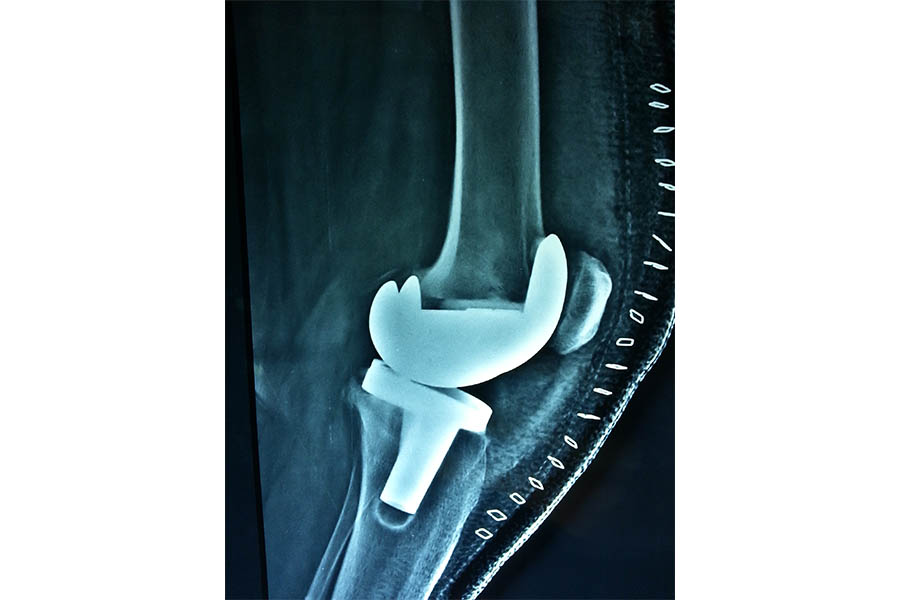

Total Elbow Replacement

Case 1